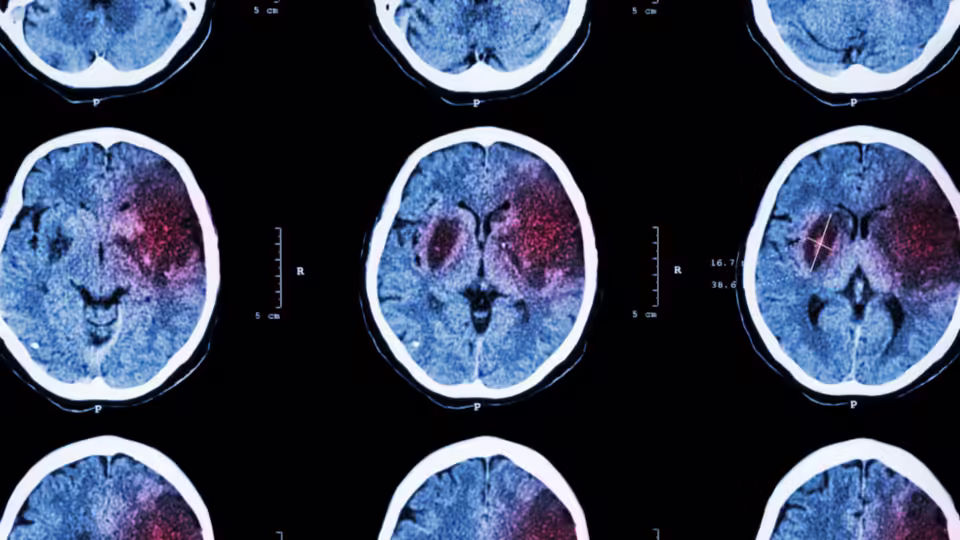

Existen dos formas principales de ACV.

- El isquémico, que ocurre cuando un coágulo bloquea una arteria cerebral e impide que la sangre llegue al tejido.

- El hemorrágico, que se produce cuando un vaso se rompe y provoca una hemorragia dentro del cerebro.